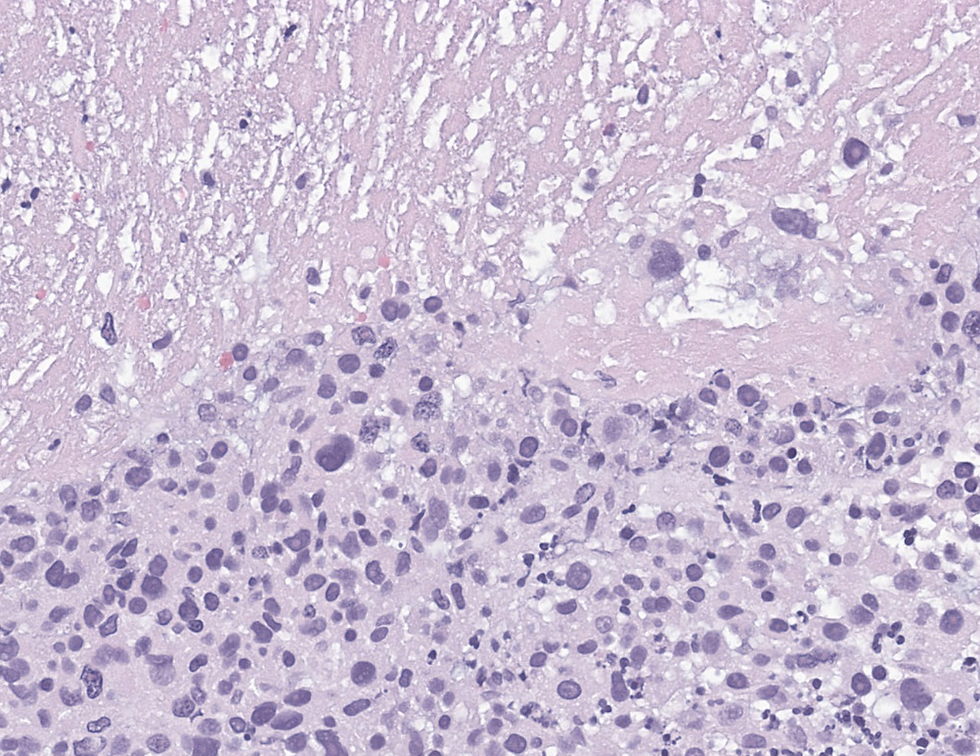

A 70-year-old women who presented with abnormal uterine bleeding and she underwent an endometrial biopsy. The tumor is strong and diffusely positive for p16.

The correct answer is E, leiomyosarcoma and the diffusely p16 staining is not specific, p16 is frequently positive in high grade LMS. On the contrary, p16 loss is associated with CDKN2A deletion that can be associated with poor prognosis. The case showed tumor-type of necrosis and a high grade round, oval, spindle cell with cytoplasm. The leiomysarcoma was diagnosed based on diffuse positivity of desmin and negative for PAX8, keratin, wild type p53.